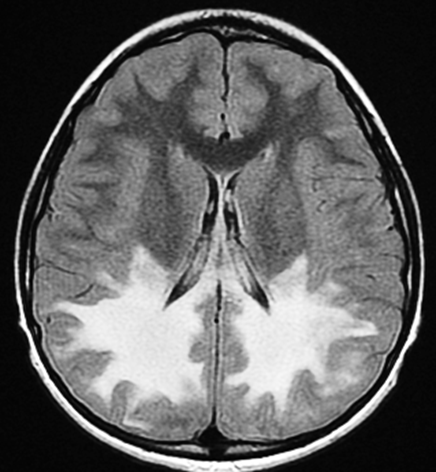

This article focuses on the brain CT and MRI findings of leukodystrophy, illustrated by a 30-year-old male patient. The radiological features are discussed along with pathophysiological mechanisms, epidemiology, clinical manifestations, and the latest therapeutic strategies.

A 30-year-old man underwent brain CT for evaluation of progressive cognitive decline. Compared to normal axial slices through the midbrain, the patient's images revealed:

·         Global ventricular enlargement and CSF space expansion (marked by red and blue arrows)

·         Diffuse skull thickening, a compensatory finding often associated with chronic brain atrophy

·         Overall pattern consistent with leukodystrophy

These radiologic signs, combined with clinical history, support the diagnosis.

MRI Features:

·         T2/FLAIR hyperintensities in the periventricular and deep white matter

·         Involvement of the corpus callosum, internal capsule, and centrum semiovale

·         Possible sparing of U-fibers (in certain subtypes)

·         Symmetrical pattern typical of metabolic disorders